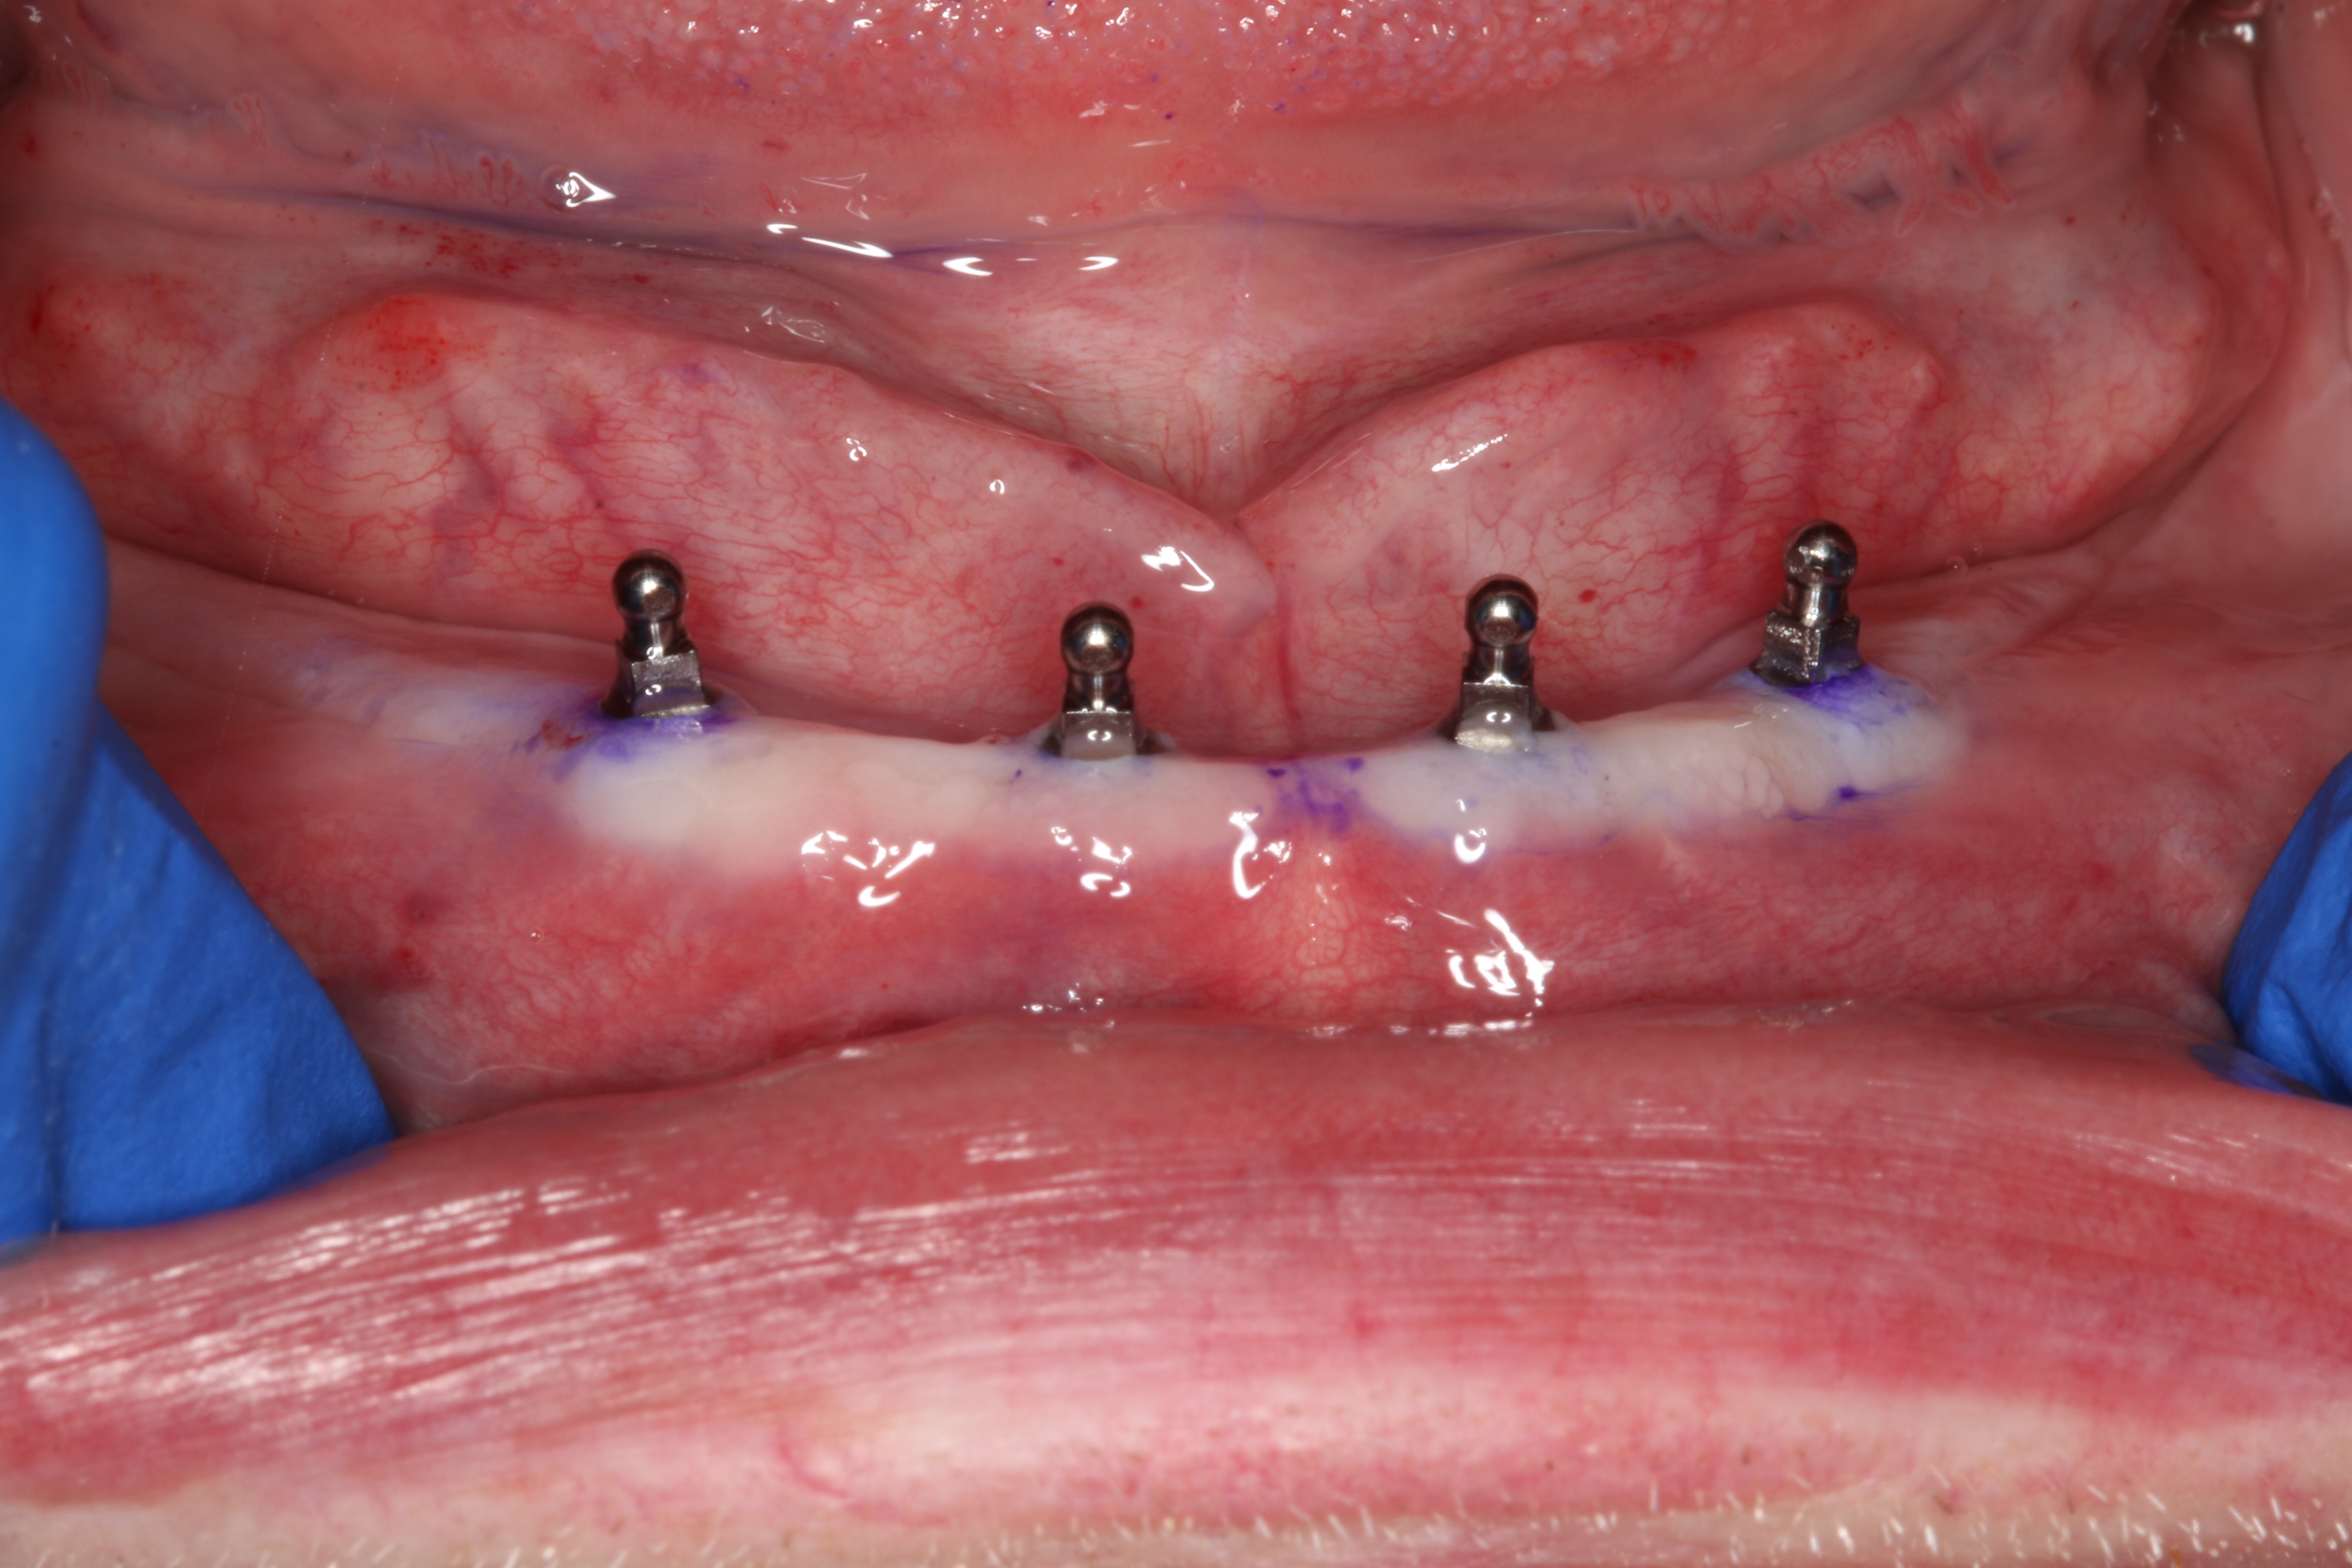

A sterile operating environment was established. Prior to administering anesthesia the location of the mental foramen and the exiting neurovascular bundle was established by palpating the facial aspect of the mandible; this procedure was performed in conjunction with the cross-sectional CBCT imaging. If this technique is inadequate, a radiographic splint can be used to further verify the position of the mental foramen; often, a patient’s existing mandibular denture can be modified for this purpose. A surgical marker was used to mark the proposed implant positions with at least 3-mm inter-implant spacing (Figure 2). Establishing the position of the mental nerve prior to administering local anesthesia is necessary, because the injection site will become filled with anesthetic solution, and/or submucosal hematoma will interfere with accurate palpation. Sufficient pain control was achieved via infiltration of local anesthetic in the area of the mental foramen as well as along the crest of the anterior mandible. Care was taken to minimize the patient’s exposure to epinephrine.

Fig 2. Preoperative view of mandible with proposed implant locations marked.

Figure 2